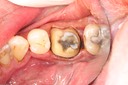

Alan Chinn #28 pre-op

Alan Chinn #28 caries removal